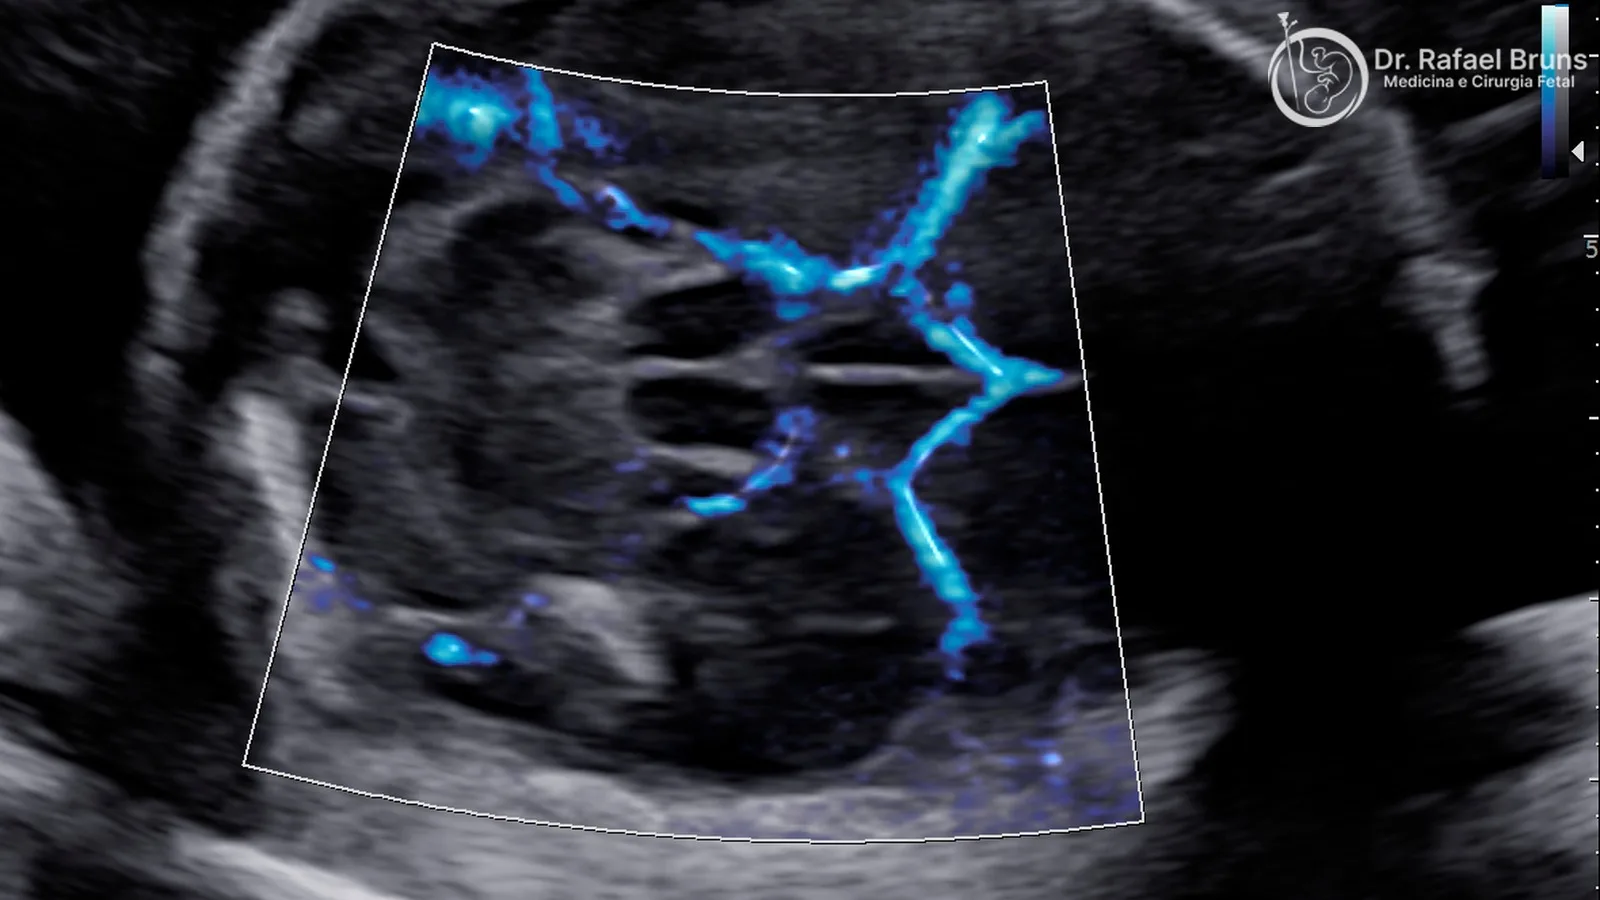

Doppler colorido (ou color Doppler): mapeia o fluxo em toda uma região ao mesmo tempo, colorindo os vasos conforme a direção do sangue — vermelho para um sentido, azul para o outro. Ele é fundamental para localizar vasos, identificar estruturas cardíacas fetais, avaliar o cordão umbilical e orientar a medição espectral. No exame do coração fetal, o Doppler colorido permite visualizar como o sangue se move pelas câmaras e válvulas com precisão impossível de obter só com a imagem em escala de cinza.

Doppler color no coração fetal: uma janela para a ecocardiografia

Além dos vasos, o Doppler colorido é indispensável na avaliação do coração fetal. Em uma ecocardiografia fetal completa, ele é usado para:

- Confirmar a direção do fluxo nas câmaras cardíacas e grandes vasos

- Identificar regurgitações valvares — quando uma válvula não fecha corretamente e o sangue reflui

- Detectar obstruções ao fluxo em aorta ou artéria pulmonar

- Visualizar o fluxo nas veias pulmonares

- Demonstrar as conexões entre ventrículos e grandes artérias em cardiopatias complexas

- Localizar comunicações anormais entre câmaras — como grandes defeitos no septo

Na triagem do morfológico do segundo trimestre, o Doppler colorido nas vias de saída e na visão de três vasos aumenta significativamente a capacidade de detectar cardiopatias congênitas que a imagem em escala de cinza pode deixar passar — incluindo transposição de grandes artérias, coarctação de aorta e estenoses valvares.

Você vai ver na tela imagens coloridas dos vasos — vermelho e azul mapeando o fluxo — e ouvir o som característico do Doppler, que varia conforme a velocidade do sangue em cada vaso. Para cada medição espectral, é necessário que o bebê esteja relativamente tranquilo e que não haja movimentação excessiva, pois isso afeta a leitura. Em alguns casos, especialmente no terceiro trimestre, pode ser necessário aguardar um momento mais calmo do bebê.